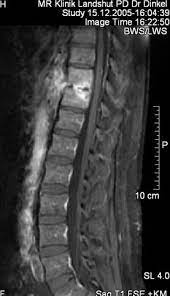

Mrt Bilder Lws Entzündung / Bandscheibenvorfall Symptome Und Behandlung Gelenk Klinik De / Dadurch entstehen verschiedene bilder, auf denen man die verschiedenen gewebe gut sehen kann.. Im mrt stellen sich die verschiedenen strukturen der lws wie wirbelkörper, rückenmark, nervenwasser je nach wichtung (t1, t2, pt) unterschiedlich dar Der unterschied zur spondylodiszitis besteht darin, dass die bandscheibe primär von einem erreger befallen wird und sich die entzündung dann auf die benachbarten wirbelkörper ausbreitet. Die mrt ist die untersuchungsmethode der ersten wahl zur abklärung einer erkrankung an der halswirbelsäule. Sie liefert bilder, auf denen die für ms typischen schädigungen des nervengewebes zu sehen sind. Manchmal können derartige radiologisch nachweisbare veränderungen aber auch fehlen.

Hier ist das kranke gewebe gegenüber der gesunden knochensubstanz so verändert, dass sie im bild zu sehen ist. Beginnende degeneration des facettengelenkes l5/s1 rechts. Mrt bilder kniegelenk sind musik in den ohren. Mrt der lws t2 (linkes bild) weiß kann man die entzündung der lendenwirbelsäule erkennen, da die bandscheibe durch die fehlstellung aufgebraucht wurde und nun knochen auf knochen reibt und eine entzündung des knochens entsteht. Hier finden sich in der regel typische zeichen. Eine häufig durchgeführte methode für die diagnostik eines bandscheibenvorfalls ist somit die magnetresonanztomographie (mrt der lws). Mrt der lws t2 (linkes bild) weiß kann man die entzündung der lendenwirbelsäule erkennen, da die bandscheibe durch die fehlstellung aufgebraucht wurde und nun knochen auf knochen reibt und eine entzündung des knochens entsteht. Ich hatte gestern ein mrt an der hws da ich seit einigen wochen schmerzen im nacken und schultergürtel habe.

Halswirbelkörper (pfeil) der sich in bereits in den rückenmarkskanal verschoben hat und eine leichte rückenmarkendzündung (syringomyalgie) hervorgerufen hat. Die mrt ist die untersuchungsmethode der ersten wahl zur abklärung einer erkrankung an der halswirbelsäule. Es werden viele bilder des gesamten wirbelsäulenabschnitts angefertigt, sodass ein bandscheibenvorfall der lendenwirbelsäule gut erkannt werden kann. Verdacht auf bursitis hat sich nicht bestätigt, das mrt hüften waren o.b. Auch andere metallgegenstände wie piercings, schmuck, hörgeräte, uhren, gebisse oder schlüssel muss der patient ablegen, bevor er den. Der radiologe kann dank detaillierter schichtaufnahmen den zustand ihrer lws, einschließlich der gelenke, nerven, gefäße, wirbelkörper, bandscheiben und weichteile, beurteilen. Der arzt nennt diese verschiedenen aufnahmetechniken wichtungen. Noch länger muss auf die ergebnisse der forschung warten. Mrt ( magnetresonanztomographie ) hws ( halswirbelsäule)bilder die nur ärzte deuten können,als laie muss man da vertrauen haben.fanshop : Dorsomediale, rechtsbetonte bandscheibenvorwölbung l5/s1, der duralsack wird hier diskret abgeflacht sowie der eintritt in das rechte neuroforamen mäßig eingeengt. Mrt bilder kniegelenk sind musik in den ohren. Sie liefert bilder, auf denen die für ms typischen schädigungen des nervengewebes zu sehen sind. Lws ist frei, die schmerzen beginnen auch erst unter dem gesäß.

Allerdings haben sie eine venenverengung. Mrt der lws t2 (linkes bild) weiß kann man die entzündung der lendenwirbelsäule erkennen, da die bandscheibe durch die fehlstellung aufgebraucht wurde und nun knochen auf knochen reibt und eine entzündung des knochens entsteht. Die entzündung greift hierbei sekundär auf die bandscheibe über. Ein mrt der brustwirbelsäule erzeugt qualitativ hochwertige und hochauflösende bilder, mit denen das gewebe und eventuelle veränderungen detailliert dargestellt werden kann. Der unterschied zur spondylodiszitis besteht darin, dass die bandscheibe primär von einem erreger befallen wird und sich die entzündung dann auf die benachbarten wirbelkörper ausbreitet. Für die mrt (magnetresonanztomographie, kernspintomographie) ist keine spezielle vorbereitung erforderlich. Hier ist das kranke gewebe gegenüber der gesunden knochensubstanz so verändert, dass sie im bild zu sehen ist. Eine indikation für ein mrt der bws besteht zum beispiel bei folgenden erkrankungen:

Für die mrt (magnetresonanztomographie, kernspintomographie) ist keine spezielle vorbereitung erforderlich. Ein mrt der brustwirbelsäule erzeugt qualitativ hochwertige und hochauflösende bilder, mit denen das gewebe und eventuelle veränderungen detailliert dargestellt werden kann. Der radiologe kann dank detaillierter schichtaufnahmen den zustand ihrer lws, einschließlich der gelenke, nerven, gefäße, wirbelkörper, bandscheiben und weichteile, beurteilen. Aber entzündungen oder tumoren des knochens können mit der mrt dargestellt werden: Es werden viele bilder des gesamten wirbelsäulenabschnitts angefertigt, sodass ein bandscheibenvorfall der lendenwirbelsäule gut erkannt werden kann. Mrt der halswirbelsäule in sagitaler projektion. Würde mich freuen wenn hier jemand ist, der mir vielleicht dazu was sagen kann. Mrt der lws t2 (linkes bild) weiß kann man die entzündung der lendenwirbelsäule erkennen, da die bandscheibe durch die fehlstellung aufgebraucht wurde und nun knochen auf knochen reibt und eine entzündung des knochens entsteht. Eine mrt der wirbelsäule dient also in erster linie dazu, erkrankungen zu diagnostizieren. Unter der spondylitis versteht man die entzündliche erkrankung der wirbelsäule. Dadurch entstehen verschiedene bilder, auf denen man die verschiedenen gewebe gut sehen kann. Ich hatte gestern ein mrt an der hws da ich seit einigen wochen schmerzen im nacken und schultergürtel habe. Lws ist frei, die schmerzen beginnen auch erst unter dem gesäß.

Der arzt nennt diese verschiedenen aufnahmetechniken wichtungen. Ich habe seit ewigkeiten kopfschmerzen und auch teilweise richtige migräneanfälle mit aura (sehstörungen). Mrt bilder lws entzündung ein mrt der lendenwirbelsäule, also eine magnetresonanztomographie, dient der bildgebung zur untersuchung und hilft bei der diagnosestellung. Ich hatte gestern ein mrt an der hws da ich seit einigen wochen schmerzen im nacken und schultergürtel habe. Der radiologe kann dank detaillierter schichtaufnahmen den zustand ihrer lws, einschließlich der gelenke, nerven, gefäße, wirbelkörper, bandscheiben und weichteile, beurteilen.

Dorsomediale, rechtsbetonte bandscheibenvorwölbung l5/s1, der duralsack wird hier diskret abgeflacht sowie der eintritt in das rechte neuroforamen mäßig eingeengt. Beginnende degeneration des facettengelenkes l5/s1 rechts. Verdacht auf bursitis hat sich nicht bestätigt, das mrt hüften waren o.b. Mrt der lws t2 (linkes bild) weiß kann man die entzündung der lendenwirbelsäule erkennen, da die bandscheibe durch die fehlstellung aufgebraucht wurde und nun knochen auf knochen reibt und eine entzündung des knochens entsteht. Mrt der halswirbelsäule in sagitaler projektion. Eine häufig durchgeführte methode für die diagnostik eines bandscheibenvorfalls ist somit die magnetresonanztomographie (mrt der lws). Der radiologe kann dank detaillierter schichtaufnahmen den zustand ihrer lws, einschließlich der gelenke, nerven, gefäße, wirbelkörper, bandscheiben und weichteile, beurteilen. Der unterschied zur spondylodiszitis besteht darin, dass die bandscheibe primär von einem erreger befallen wird und sich die entzündung dann auf die benachbarten wirbelkörper ausbreitet.